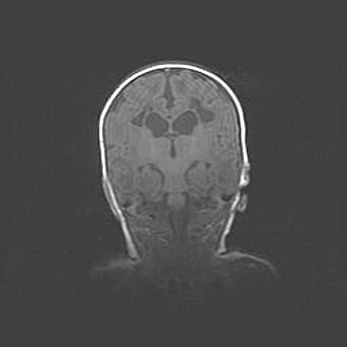

Множественные кисты обоих полушарий головного мозга, наибольшая из них в правой затылочной области. Ассиметричная атрофическая гидроцефалия.

Возраст: 7 месяцев

Вес: 5660 г

Пол: мужской

Окружность головы: 41,5 см

Срок гестации: 28-29 недель

Кисты головного мозга развиваются в результате многоочаговых некрозов вещества мозга и возникают вследствие перенесенной перинатальной инфекции, менингитов, энцефалитов, асфиксии, родовой травмы, расстройств мозгового кровообращения различного генеза. Образованию кист в веществе головного мозга плодов и новорожденных способствуют такие факторы, как высокое содержание в нем воды, недостаточная (или отсутствие) миелинизация и слабая астроглиальная реакция на повреждение.

Кисты могут сочетаться с гидроцефалией и другими поражениями головного мозга.